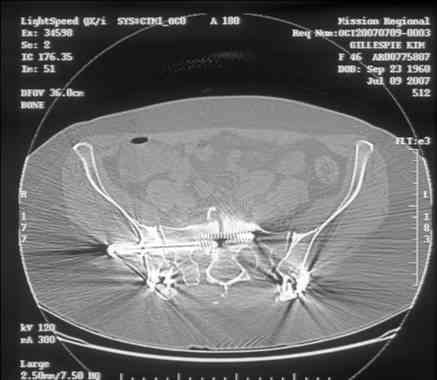

Looking for advice. This is a 48 yo non-smoking female s/p MCC 10 months ago. I do not have the initial injury films. She underwent ORIF as shown on attached file. She is having continued pain in low back/sacral region. Worse with sitting and prolonged walking. Has had pain since surgery. All of her wounds have healed uneventfully. Also has right hip pain laterally. No groin pain. Not aggravated with ROM of the hip. Infection work-up has been negative.

Any thoughts on the broken plate on the pelvic brim and the non-union on the anterior column. Doesn't seem like she's have pain from there.

Here is a magnified view. Sorry about the quality but the CT was scanned into our system.